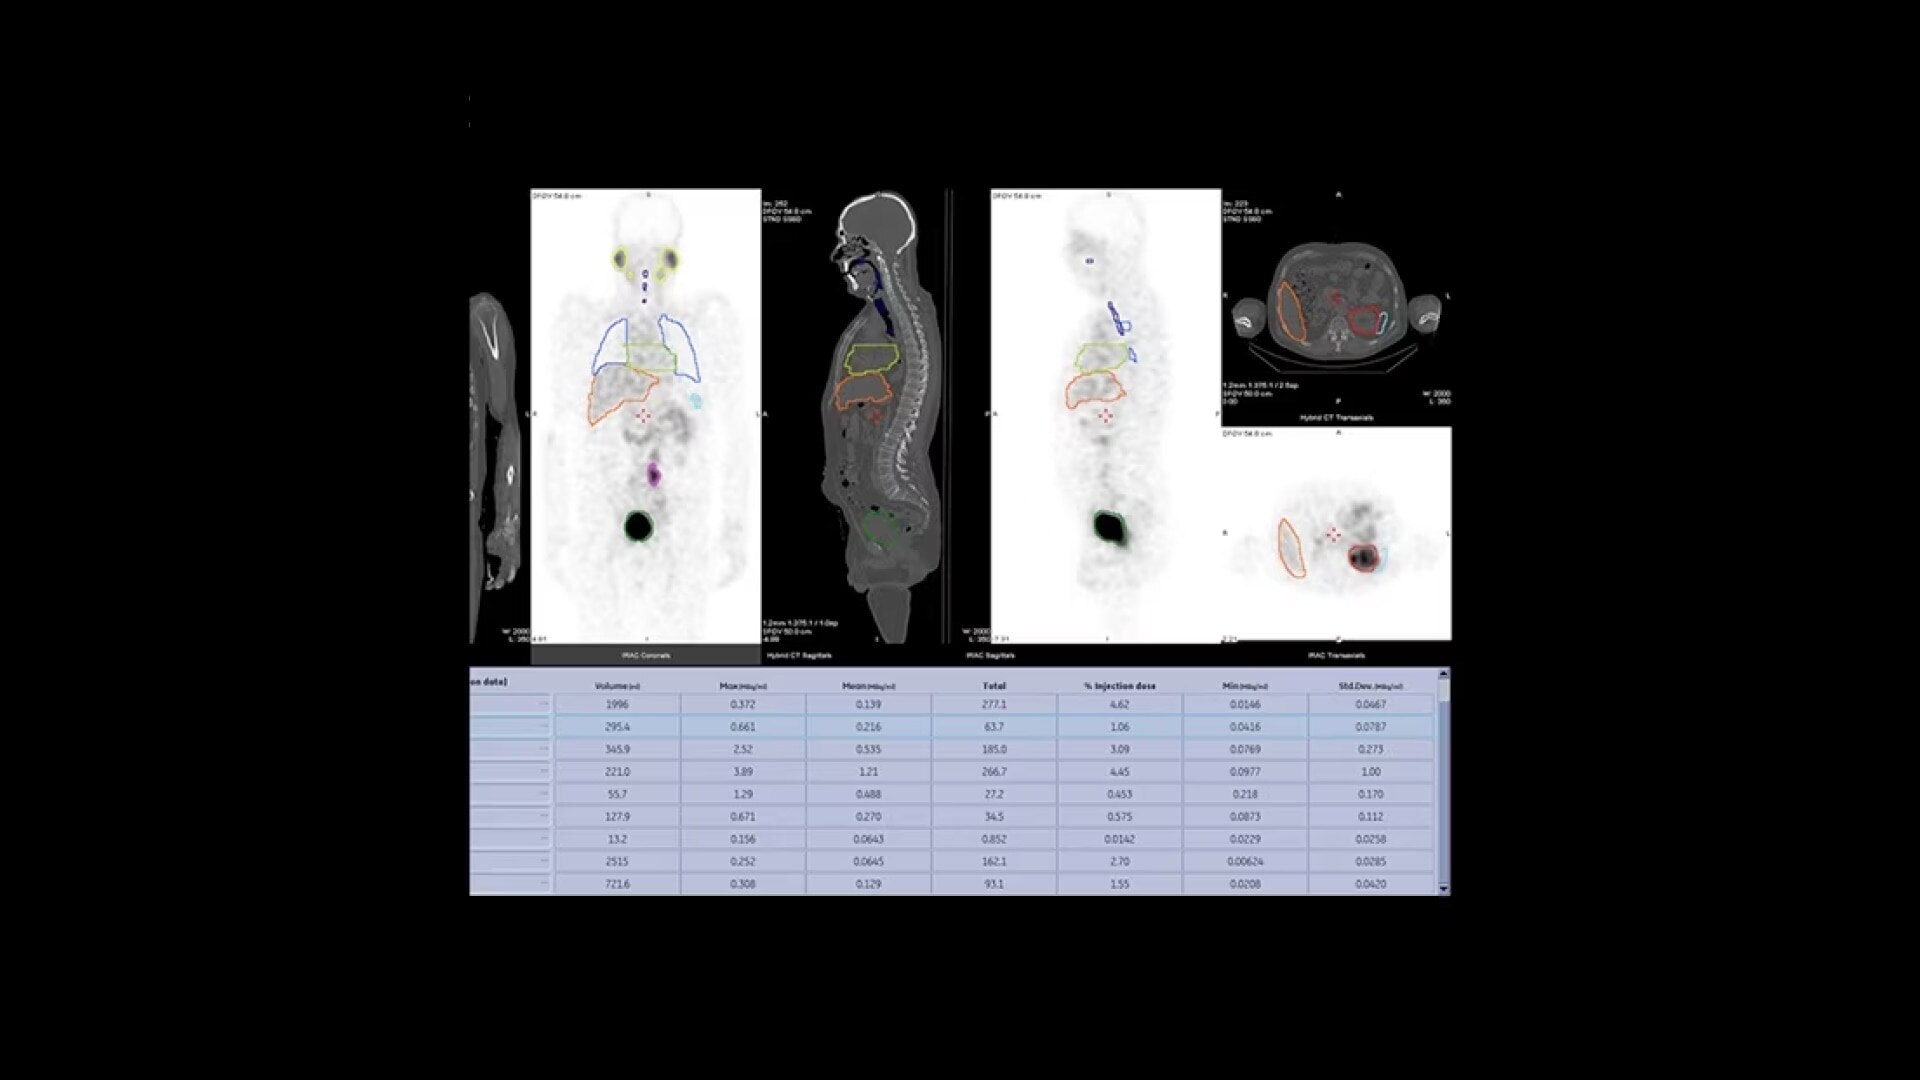

A simpler way to bring everything together

Q.Volumetrix MI is an Xeleris 4 DR application that integrates SUV measurements directly into the volume viewer. It allows you to see both the image and the SUV simultaneously instead of having to switch back and forth between two separate applications. Then, with SmartConsole, your quantitative SPECT/CT studies are automatically transferred directly to the PACS or other pre-defined DICOM destination. These resource-saving improvements allow you to expand your services to offer these advanced protocols without breaking your schedule.